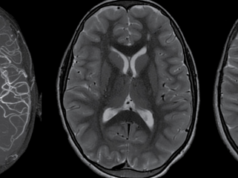

Aceste manifestari ale unui copil foarte mic de abia născut sunt un motiv de îngrijorare pentru familie. De cele mai multe ori părinții înregistrează aceste evenimente și vin cu filmarea la consultație. Este foarte important să vedem aceste filmări ca să înțelegem mai bine ce ne relatează familia. Cel mai des aceste mișcări bruște se confundă cu cele care apar în cadrul unei epilepsii neonatale. Dar, uneori, nici doctorul nu-și poate da seama dacă este mioclonus neonatal benign de somn sau este vorba de crize epilpetice numite mioclonii. Din acest motiv este important să se efectueze o electroencefalogramă în somn și în veghe. Dacă surprindem acest eveniment în timpul înregistrării este foarte bine. Oricum, electroencefalograma atât în timpul manifestării cât și în absența ei este normală în cazul mioclonusului neonatal benign de somn. Copilul este normal neurologic.